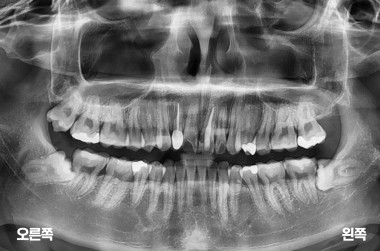

3

사랑니 3개 발치